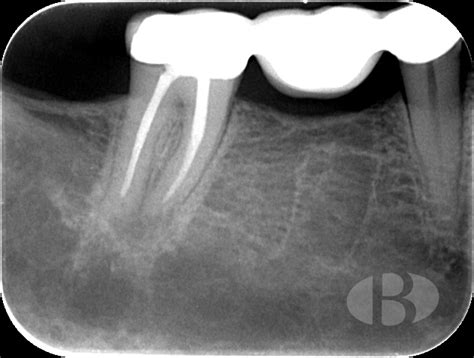

Lesión periapical en una radiografía dental.

En sus fases iniciales, una lesión periapical puede no presentar síntomas. El diagnóstico se basa en una combinación de exploración clínica y pruebas radiográficas. Una radiografía periapical permite observar la zona alrededor del ápice radicular y detectar lesiones de tipo inflamatorio o infeccioso.